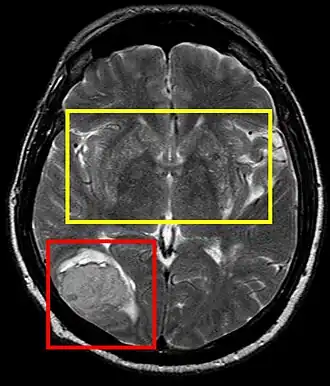

La hipertensión arterial persistente puede causar un accidente cerebrovascular trombótico o embólico, infartos lacunares o un accidente cerebrovascular hemorrágico con hematoma intracerebral, entre otros. Tanto la presión sistólica y diastólica elevadas son perjudiciales; una presión diastólica de más de 100 mmHg y una presión sistólica de más de 160 mmHg han dado lugar a una incidencia significativa de enfermedades cerebrovasculares. Otras manifestaciones de la hipertensión incluyen la encefalopatía hipertensiva, lesiones microvasculares cerebral y la demencia de origen vascular como consecuencia de múltiples infartos del sistema nervioso central.